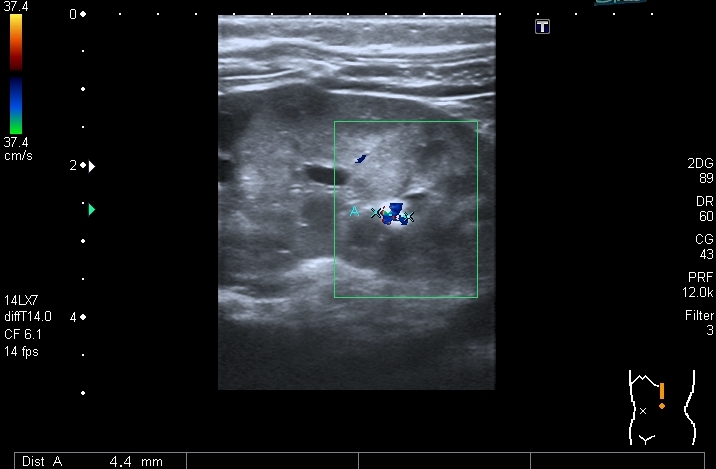

В нижней чашечке левой почки - конкремент до 5 мм

Конкремент даёт твитлинг - артефакт